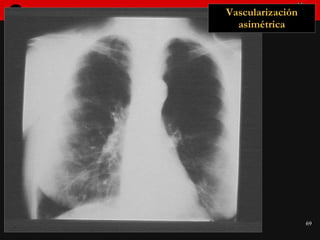

Patrón de vascularización pulmonar asimétrico Distribución vascular asimétrica Sin asimetrías en el parénquima

Vascularización asimétrica